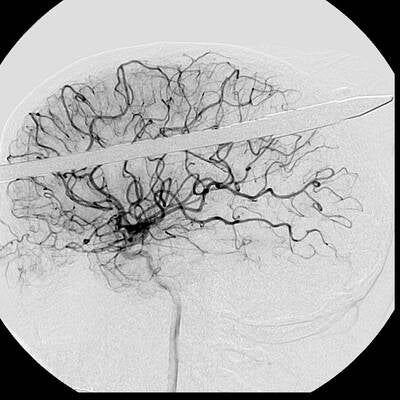

In einer Notoperation kämpften die Ärzte um das Leben von Eduardo Leite. Sie öffneten den Schädel und entschieden sich, die Stange aus der gleichen Richtung zu entfernen, aus der sie in den Kopf eingedrungen war.

Nach fünf Stunden hatten die Ärzte das Leben des Mannes gerettet – Folgeschäden dürfte er nur in geringer Form durchleiden müssen. „Es war wirklich ein Wunder“, so der betreuende Arzt Luiz Essinger.